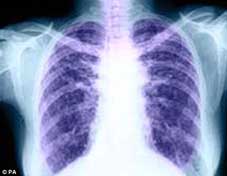

Lần đầu tiên, một lá phổi hiến tặng bị tổn thương đã được chỉnh sửa và ghép cho bệnh nhân. Bình thường phổi hiến tặng nếu không đạt tiêu chuẩn sẽ bị bỏ đi. Tuy nhiên, áp dụng kỹ thuật mới kết hợp thuốc với tế bào gốc, các bác sĩ Canada đã biến lá phổi suýt bị vứt bỏ thành lá phổi đủ tiêu chuẩn ghép cho bệnh nhân.

Phổi hiến tặng thường được lấy từ người tử vong do chấn thương sọ não để ghép cho bệnh nhân. Tuy nhiên, do khi ngừng hoạt động não bộ thường giải phóng các men (enzyme) gây viêm nhiễm nên chỉ khoảng 15% phổi đáp ứng tiêu chuẩn trong phẫu thuật ghép tạng. Những phổi tốt sẽ được trữ lạnh và có thể dùng để ghép trong vòng 6 đến 8 giờ.